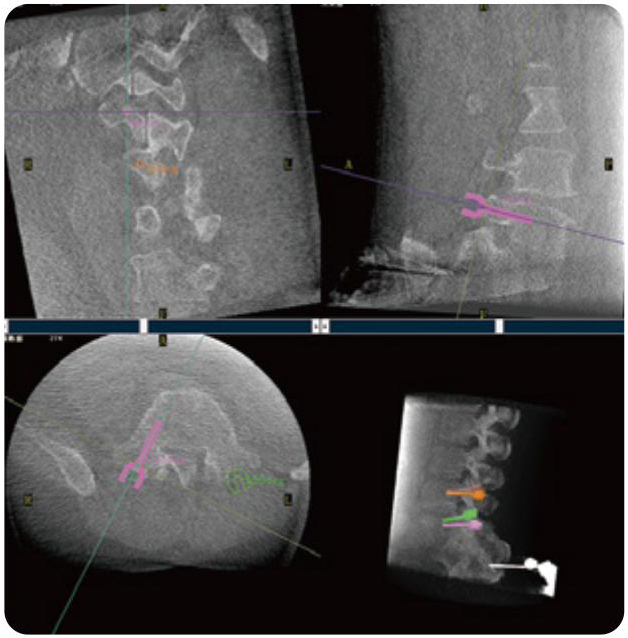

PL300B可應(yīng)用于多節(jié)段脊柱外科手術(shù),輔助醫(yī)生定位病灶部位,為脊柱外科手術(shù)(經(jīng)皮椎體成形術(shù)、椎弓根螺釘內(nèi)固定術(shù)等術(shù)式)提供術(shù)前手術(shù)流程規(guī)劃、入釘位置、角度可視化引導(dǎo),模擬仿真入釘輔助。

PL300B搭配普愛醫(yī)療自主研發(fā)生產(chǎn)的平板3D C形臂,借助一體化自適應(yīng)配準(zhǔn)( 軌跡配準(zhǔn))技術(shù),通過追蹤C(jī)形臂三維采集軌跡,自動(dòng)完成圖像坐標(biāo)建立和系統(tǒng)坐標(biāo)配準(zhǔn)。配準(zhǔn)精度更高,操作步驟少,系統(tǒng)運(yùn)作效率高。